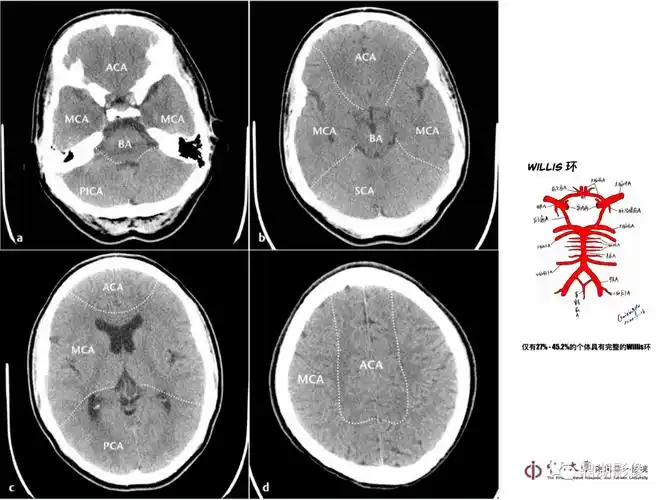

急性缺血性脑卒中多模式头颅ct图像解读